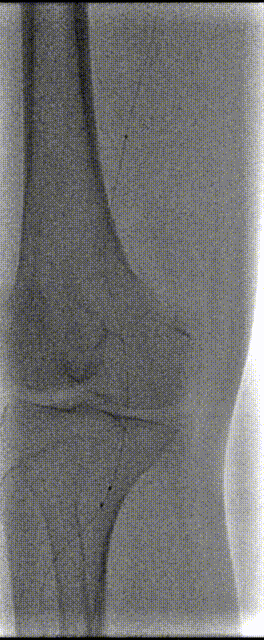

4.抽吸后造影见:腘动脉血流恢复,管腔局部可见狭窄,沿导丝导入球囊扩张导管(4*200mm,巴德,6atm,3min)于腘动脉病变内分段扩张。扩张后造影见:右股腘动脉至胫前动脉远端血流恢复。

患者术后自述右下肢疼痛较术前明显缓解,双下肢皮温无明显差别。